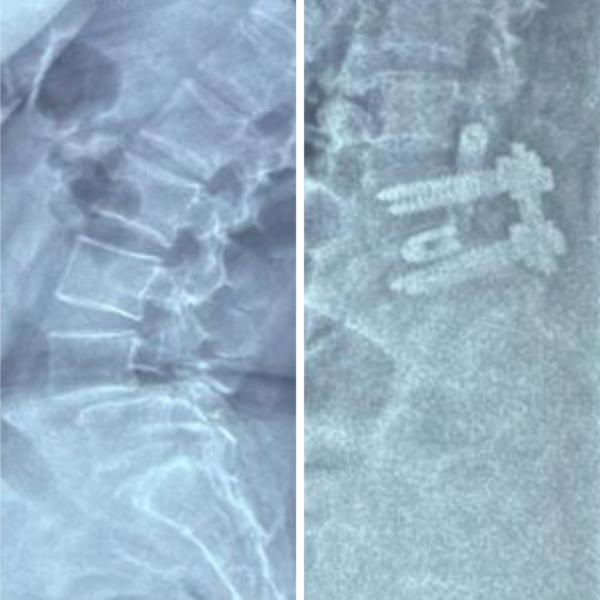

TLIF for L45 Spondylolisthesis- Spinal fusion Surg...

View Details